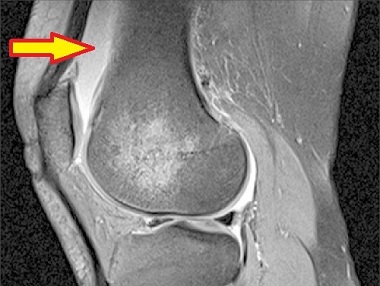

There are a number of different bursa around the knee. The suprapatellar bursa is located just above the patella (kneecap) between the quadriceps tendon and the lower end of the femur (thigh bone).

The primary function of the suprapatellar bursa is to reduce friction and provide cushioning at the front of the knee joint and protect the surrounding structures from excessive wear and tear. During activities that involve lots of bending and straightening of the knee, e.g. walking, running, and jumping, the bursa allows the quads tendon to glide over the underlying bone, ensuring smooth joint movement.

With suprapatellar bursitis, aka quadriceps tendon bursitis, irritation of the bursa causes the synovial membrane (the lining of the bursa) to produce excess lubricating fluid to try and protect the knee. This causes the bursa to swell and become inflamed, resulting in suprapatellar bursitis.